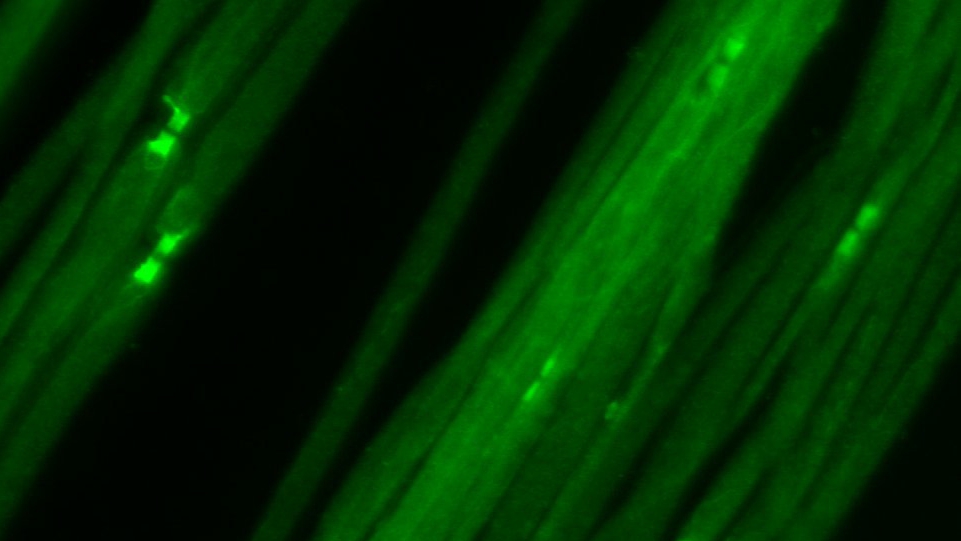

„Wir konnten feststellen, dass bei einem Teil der Patienten Antikörper gegen das Protein Caspr vorliegen“, schildert Kathrin Doppler das zentrale Ergebnis dieser Studie. Caspr ist am Aufbau der sogenannten Ranvierschen Schnürringe beteiligt – einer Struktur an der Nervenfaser, die besonders wichtig für die Weiterleitung von Nervenimpulsen ist. Die Wissenschaftlerinnen konnten zeigen, dass bei Patienten mit Antikörpern gegen Caspr der Aufbau der Ranvierschen Schnürringe zerstört wird und die Nervenleitung stark beeinträchtigt ist.

Auch wenn Antikörper gegen Caspr nur bei einem kleinen Teil der Patienten nachweisbar sind, so sind Antikörper-assoziierte Immun-Neuropathien insgesamt vermutlich häufiger, als bislang angenommen. Caspr ist nämlich schon das dritte Protein in diesem Bereich des Ranvierschen Schnürrings, gegen das nun Autoantikörper nachgewiesen wurden. Neben den Würzburger Neurologinnen haben in den vergangenen Jahren auch Wissenschaftler aus Spanien und Japan Autoantikörper gegen zwei andere Schnürringproteine, Contactin-1 und Neurofascin-155, bei Patienten mit Immun-Neuropathien nachweisen können.